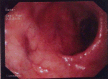

'Crohn's disease' is an inflammatory granulomatous disease of the gastrointestinal tract with extra-intestinal manifestations. Oral lesions may precede the intestinal disease and serve as a source for histological diagnosis. We present a case of orofacial Crohn's disease where orofacial symptoms were present for about 13 years and occasional constipation was present, since 6 months. Oral examination plays an important role in early diagnosis of Crohn's disease. VSports手机版.